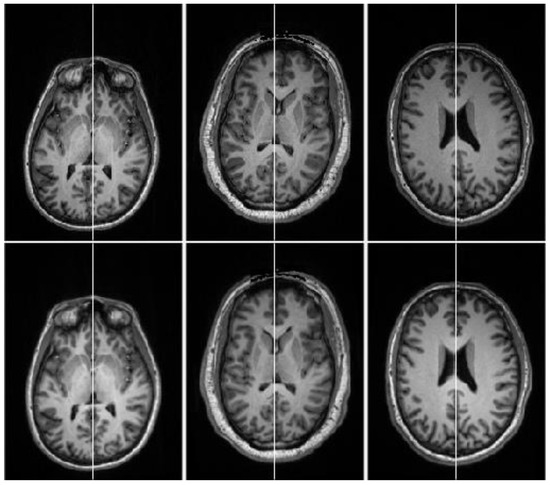

Figure 11.

Visual comparison of the proposed algorithm with Ruppert et al. algorithm for extracting the symmetric axis (MSP) from perfectly symmetric datasets: (a) input slice, (b) ground-truth slice, (c) Ruppert et al. [27] algorithm results, and (d) proposed algorithm results.

To precisely inspect the accuracy of the proposed algorithm, many illustrative slices orthogonal to the estimated MSP are displayed in Figure 11. The lines in different colors (magenta, blue and green) are the intersecting lines between the extracted MSP and the respective orthogonal slice. The first column represents the input images and the second column shows the input images with the GT MSP intersection line (magenta color line). Similarly, third and fourth columns contain the images of Ruppert et al. and proposed algorithm results, respectively. Visual comparison in Figure 11 also reveals that the proposed algorithm outperformed Ruppert et al. algorithm in terms of accuracy, both in orientation and offsets. Ruppert et al. algorithm could not always achieve a rigorous estimate of MSP, particularly when the brain MRIs underwent a considerable transformation (rotation, translation, noise).